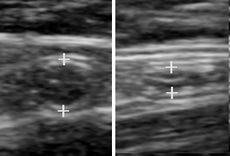

Compression ultrasonography is when the probe is pressed against the skin. This can bring the target structure closer to the probe, increasing spatial resolution of it. Comparison of the shape of the target structure before and after compression can aid in diagnosis.

A normal appendix without and with compression. Absence of comprehensibility indicates appendicitis.[4]

Compression is used in this ultrasonograph to get closer to the abdominal aorta, making the superior mesenteric vein and the inferior vena cava look rather flat.